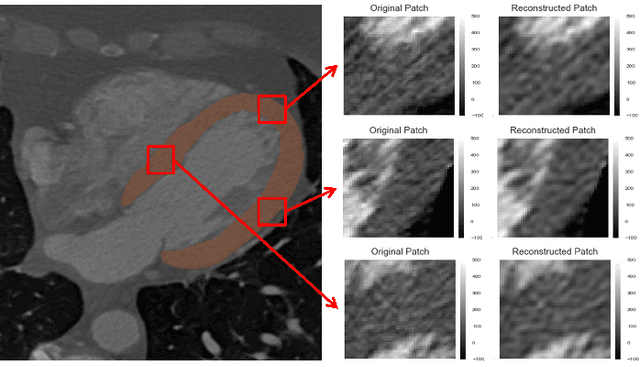

Abstract:In patients with obstructive coronary artery disease, the functional significance of a coronary artery stenosis needs to be determined to guide treatment. This is typically established through fractional flow reserve (FFR) measurement, performed during invasive coronary angiography (ICA). We present a method for automatic and non-invasive detection of functionally significant coronary artery stenosis, employing deep unsupervised analysis of complete coronary arteries in cardiac CT angiography (CCTA) images. We retrospectively collected CCTA scans of 187 patients, 137 of them underwent invasive FFR measurement in 192 different coronary arteries. These FFR measurements served as a reference standard for the functional significance of the coronary stenosis. The centerlines of the coronary arteries were extracted and used to reconstruct straightened multi-planar reformatted (MPR) volumes. To automatically identify arteries with functionally significant stenosis, each MPR volume was encoded into a fixed number of encodings using two disjoint 3D and 1D convolutional autoencoders performing spatial and sequential encodings, respectively. Thereafter, these encodings were employed to classify arteries according to the presence of functionally significant stenosis using a support vector machine classifier. The detection of functionally significant stenosis, evaluated using repeated cross-validation experiments, resulted in an area under the receiver operating characteristic curve of $0.81 \pm 0.02$ on the artery-level, and $0.87 \pm 0.02$ on the patient-level. The results demonstrate that automatic non-invasive detection of the functionally significant stenosis in coronary arteries, using characteristics of complete coronary arteries in CCTA images, is feasible. This could potentially reduce the number of patients that unnecessarily undergo ICA.